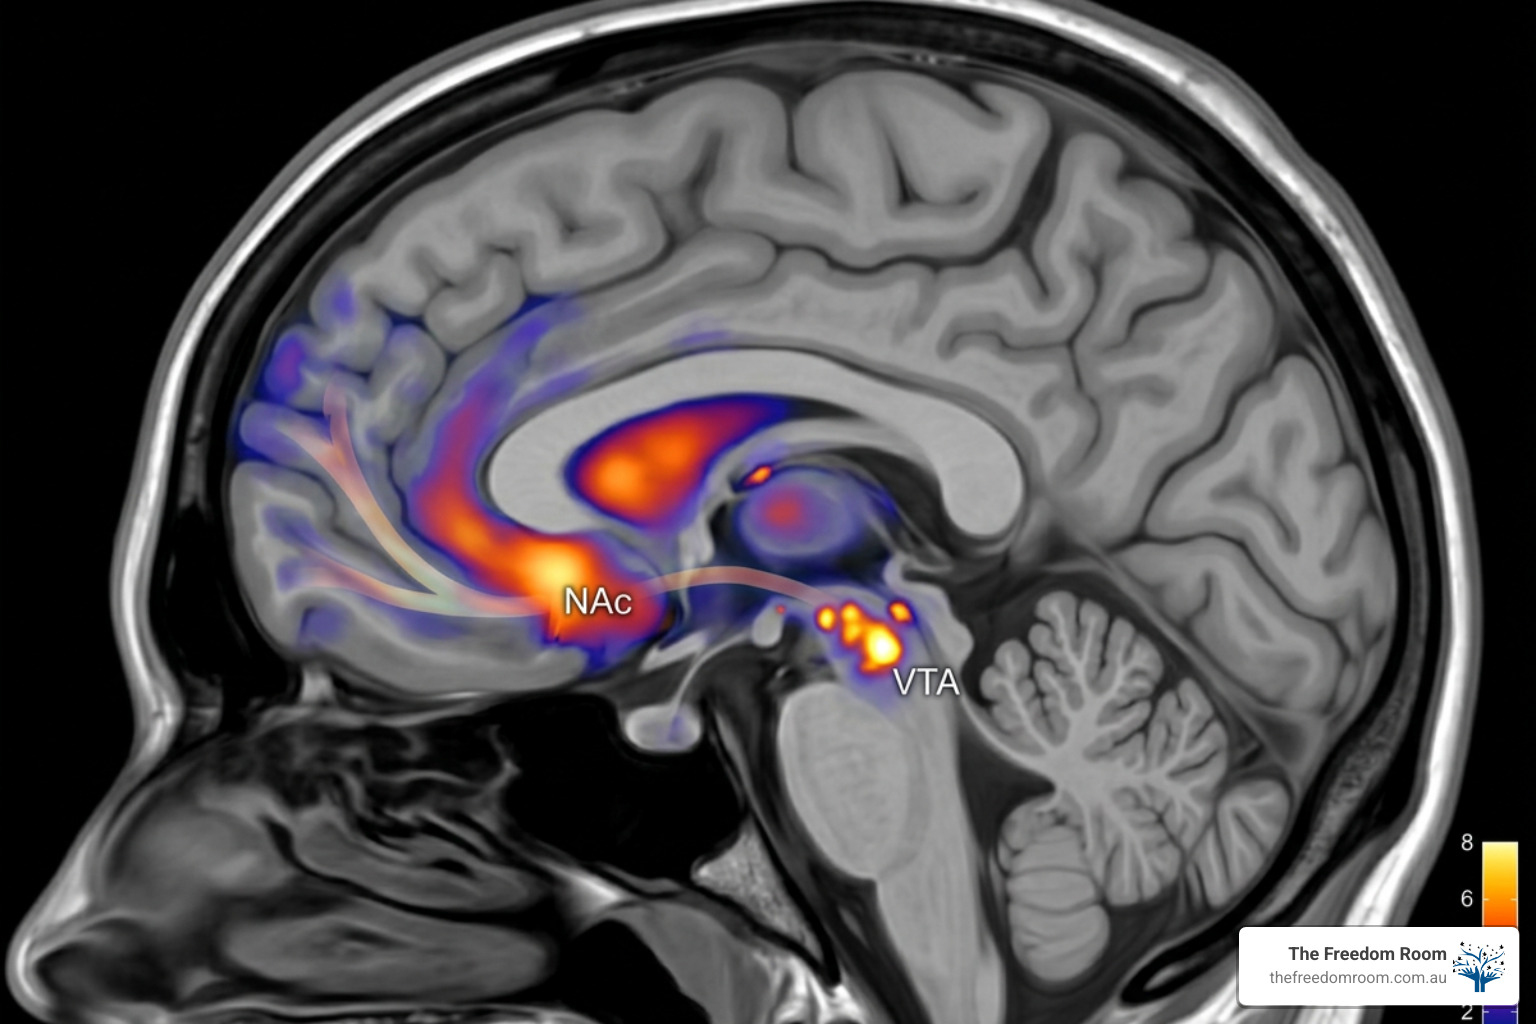

Neuroadaptation and the Stress Response

Chronic alcohol consumption does more than establish a habit: it physically alters the architecture of the brain. This process, known as neuroadaptation, modifies how an individual experiences both pleasure and pain. Specifically, long term substance use reduces the density of dopamine D2 receptors in the striatal regions and decreases dopamine transmission within the frontal lobe. This reduction can persist for several months into sobriety, leaving the brain’s reward system significantly dampened. Consequently, everyday stressors feel magnified because the brain lacks the natural neurochemicals required to buffer emotional distress.

The release of cortisol is a complex physiological event. While it assists in reacting to danger, prolonged exposure to high levels of this hormone results in significant emotional and physical strain. Laboratory studies have demonstrated that stress induced alcohol cravings are highly predictive of the volume of alcohol consumed during subsequent periods. This occurs because stress activates the same brain regions associated with substance related cues. When an individual is stressed, the brain seeks the most efficient method to return to homeostasis.

If the historical method for achieving this balance was alcohol, the brain will generate a craving as a survival signal. Understanding this mechanism helps to remove the stigma often associated with cravings: they are a biological response to a hormonal imbalance. Scientific research on stress hormones further explains how these chemical shifts can lead to a sense of hopelessness if not managed through healthy channels. By addressing the physiological root of the stress, individuals can begin to dismantle the power it holds over their choices.